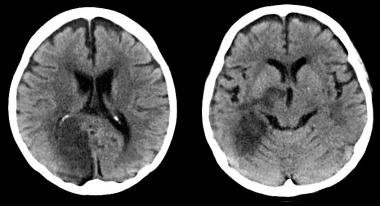

Estenosis carotídea asintomática: ¿tratamiento médico o intervención?

Dados los riesgos perioperatorios y las mejoras en la prevención del accidente cerebrovascular, la terapia médica puede ser una estrategia terapéutica aceptable. JAMA Neurology, 1º de junio de 2020.

¿Cómo afecta la enfermedad carotídea extracraneal el tratamiento de la oclusión arterial intracraneal?

La obstrucción mayor del 50% de la carótida interna extracraneal no limitó el beneficio del tratamiento intraarterial agudo en el ictus isquémico de causa intracraneal. Annals of Internal Medicine, 23 de mayo de 2017